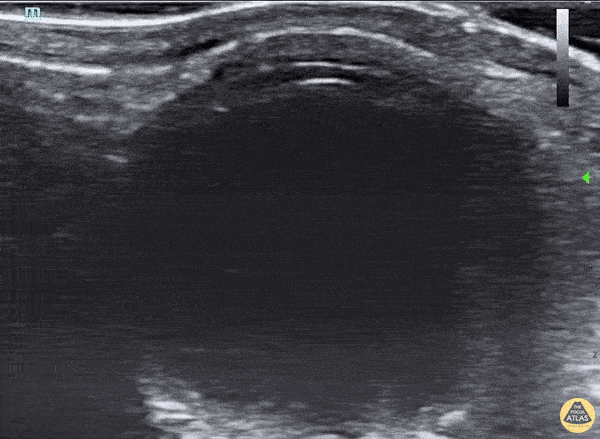

Orbital - Anterior Lens Dislocation and Retinal Detatchment

46 yo woman pmh multiple right eye surgeries presenting with atraumatic left eye pain, decreased vision, and mydriasis, which was initially concerning for acute angle-closure glaucoma. POCUS revealed anterior lens subluxation given the very shallow anterior chamber. Around 5% of acute angle-closure glaucoma is induced by lens subluxation. Retinal detachment, the hyperechoic line in the far field, can also be seen on POCUS. Ophthalmology successfully treated her with lensectomy and secondary intraocular lens implantation. Robert Adrian @RobertAdrianMD